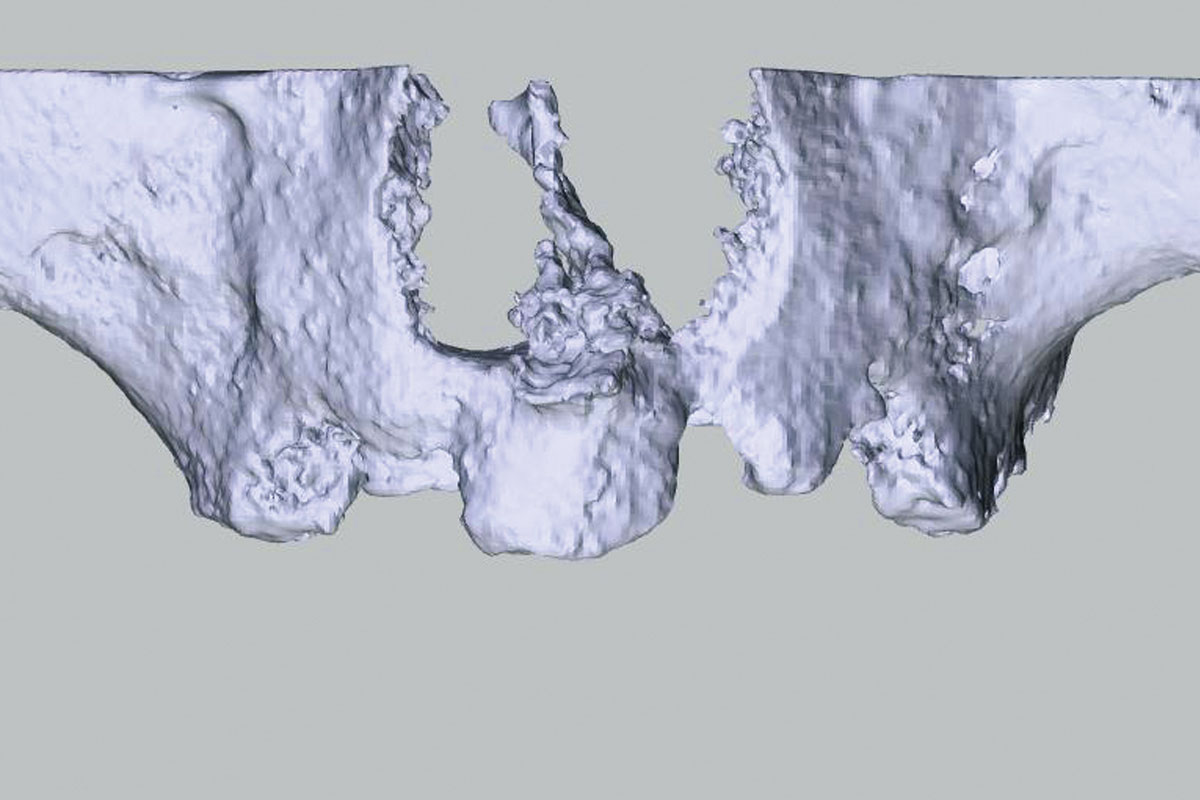

Bone defect in area 11-21 due to two lost implants (periimplantitis) after 15 years of function